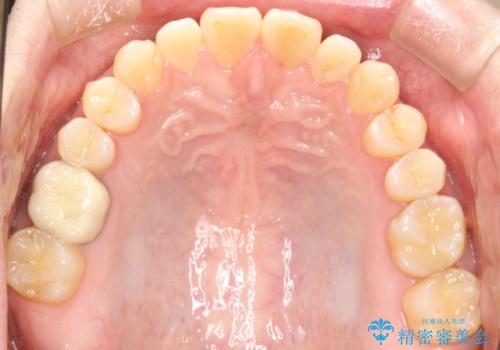

前歯の真ん中の隙間を閉じたい インビザラインによる目立たない矯正

- 上顎の正中の隙間が気になるとのことで来院されました。

下の歯と歯の間をわずかに削り、スペースを作り、正中の隙間を閉じる計画としました。

装置はインビザラインにて行いました。

インビザラインで目立たずに矯正治療を行うことができました。

使用時間を守っていただけたので、比較的スムーズに矯正を終了することができました。